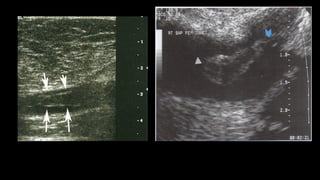

üPara demostrar la permeabilidad y competencia se realiza la

corte transversal del vaso para evitar desplazamiento.

1. Visualización

directa

del

trombo

como

estructura

ecogénica en

la

luz

de

vena.

2. Medición

los

cambios

provocados

por

presencia

(distensión

pasiva

vaso,

pérdida

compresibilidad).

3. Detección

un

cambio

en

dinámica

flujo

venoso

(ausencia

total

o

alterado

alrededor

trombo).

üPara demostrar lapermeabilidad y competencia se realiza la maniobra de compresión externa, tiene alta sensibilidad y especificidad para detectar trombosis. De preferencia se realiza en un corte transversal del vaso para evitar desplazamiento. üPara demostrar competencia valvular se utiliza la maniobra de Valsalva a través de inspiración profunda y sostenida, el flujo al Doppler color debe de cesar

CRITERIOS  DIAGNÓSTICOS  DE  TVP 1. Visualización  directa  del  trombo  como  estructura  ecogénica en  la   luz  de  la  vena. 2. Medición  de  los  cambios  provocados  por  la  presencia  del  trombo   (distensión  pasiva  del  vaso,  pérdida  de  compresibilidad). 3. Detección  de  un  cambio  de  un  cambio  en  la  dinámica  del  flujo   venoso  (ausencia  total  o  flujo  alterado  alrededor  del  trombo).